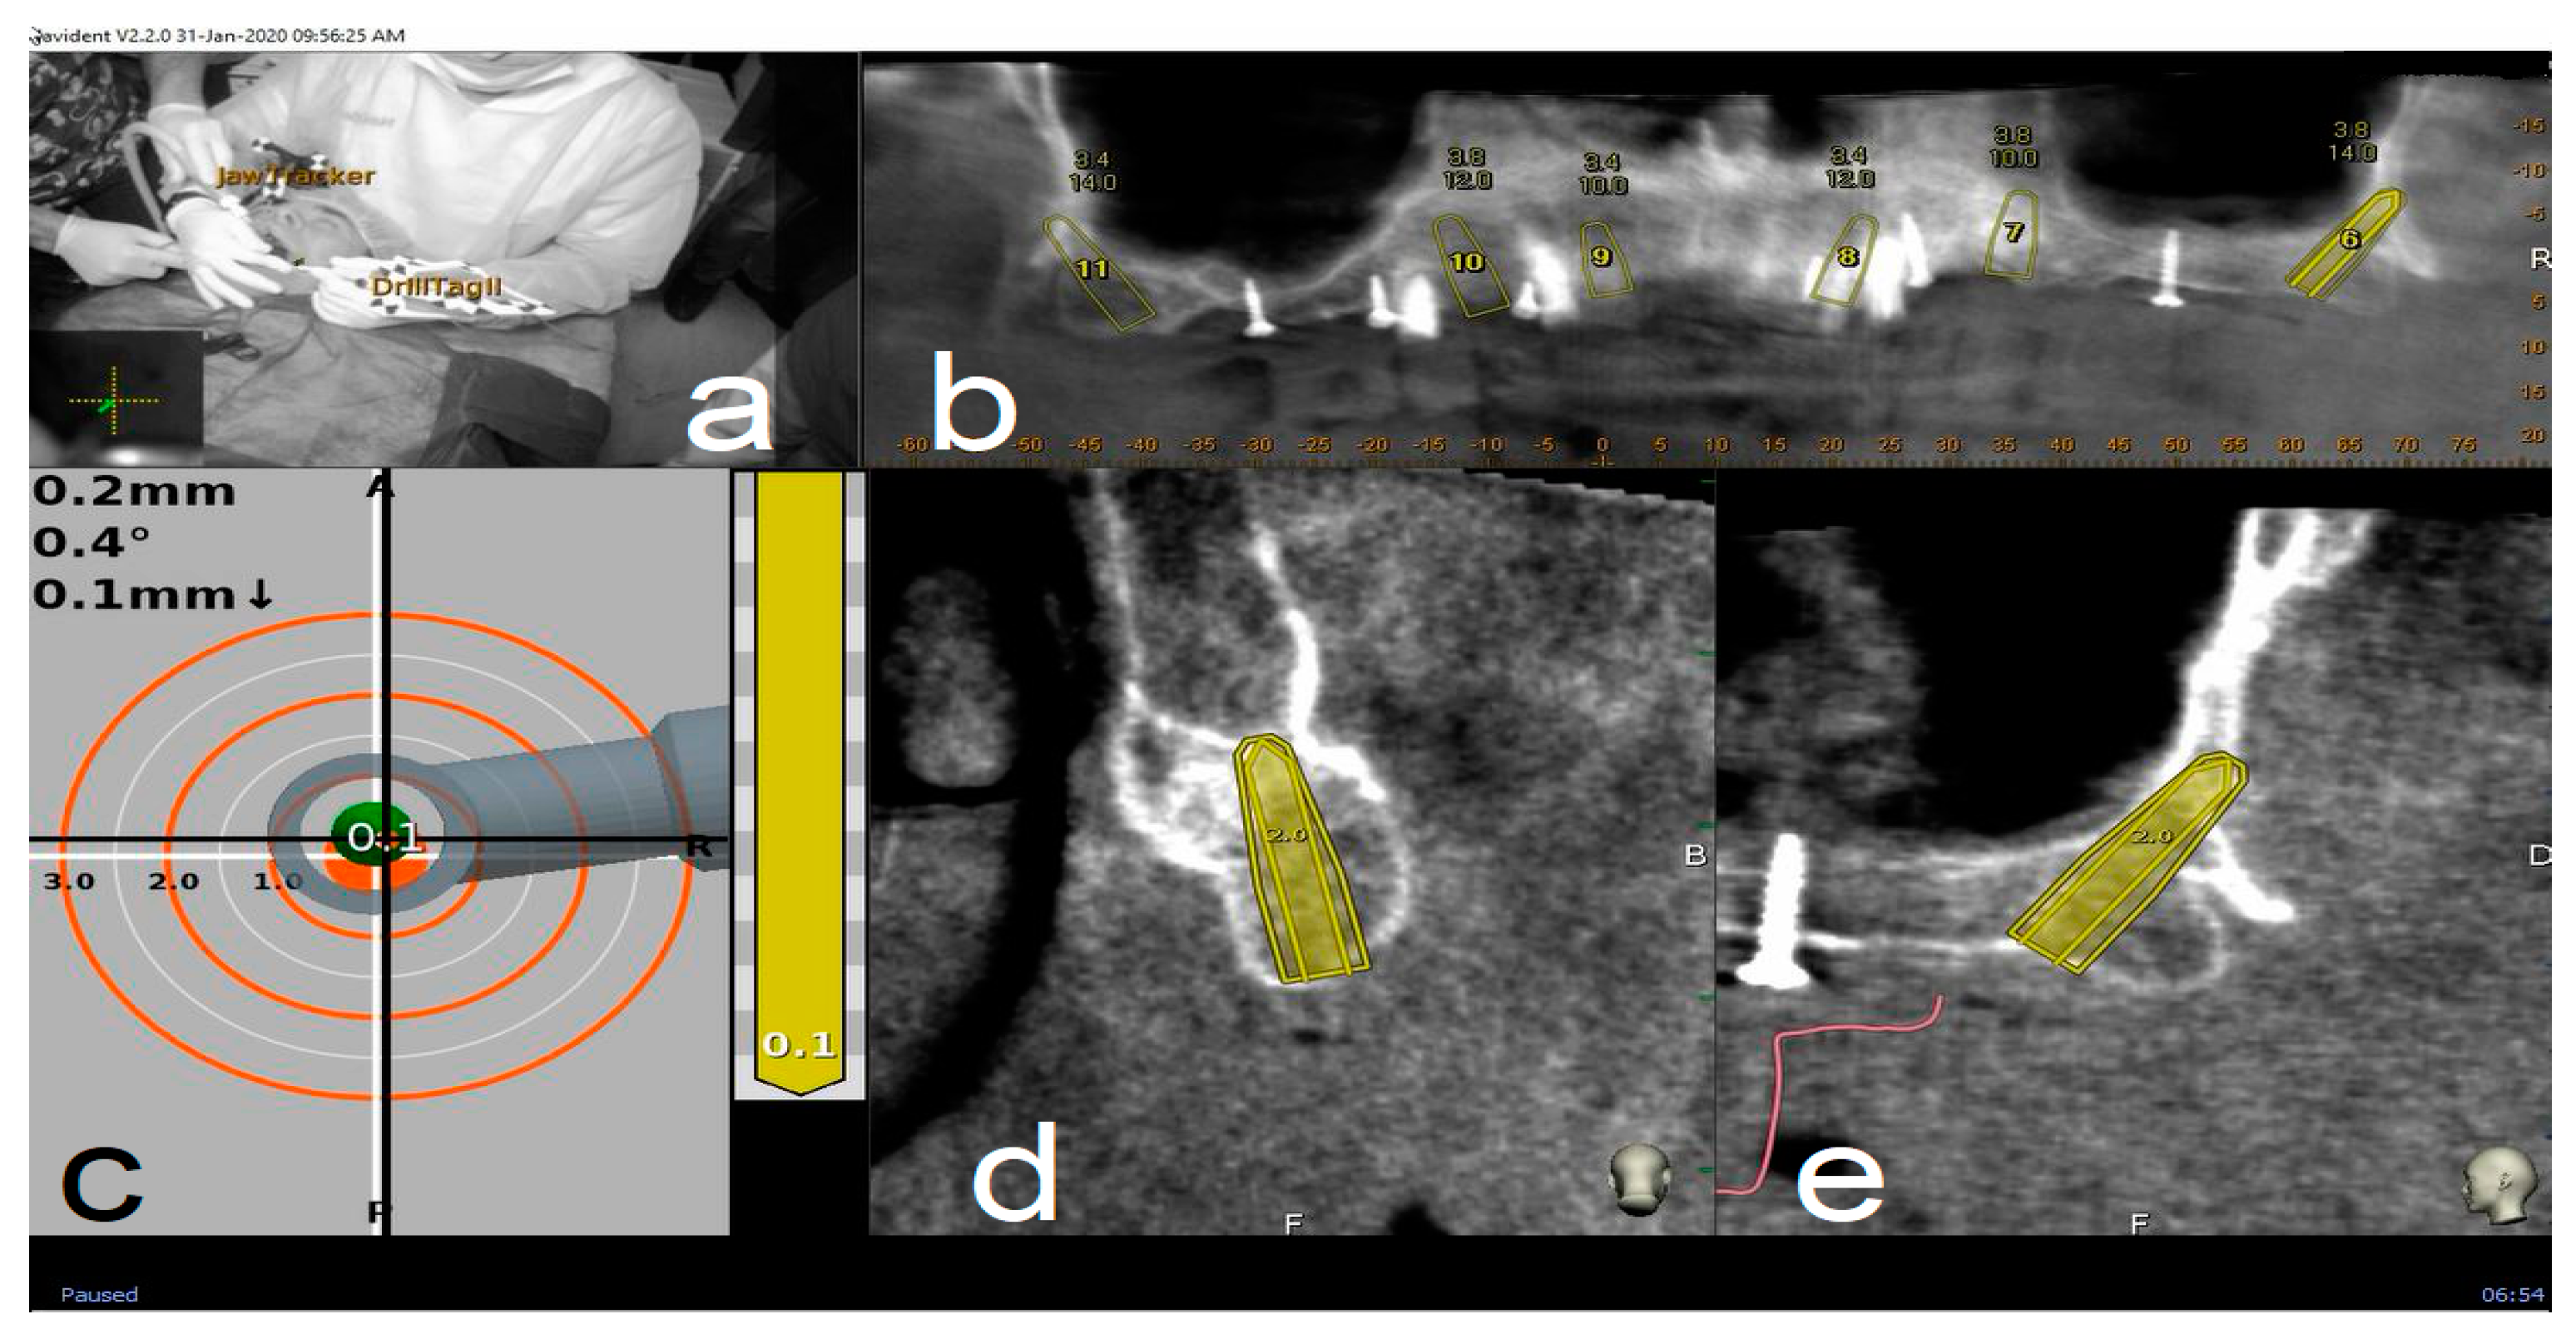

Figure 5.

Clockwise from up left. The figure indicates the several views on the screen during surgery: tracker video stream (a), panoramic view (b), target view and depth indicator (c), bucco-lingual section view (d), and mesio-distal section view (e).